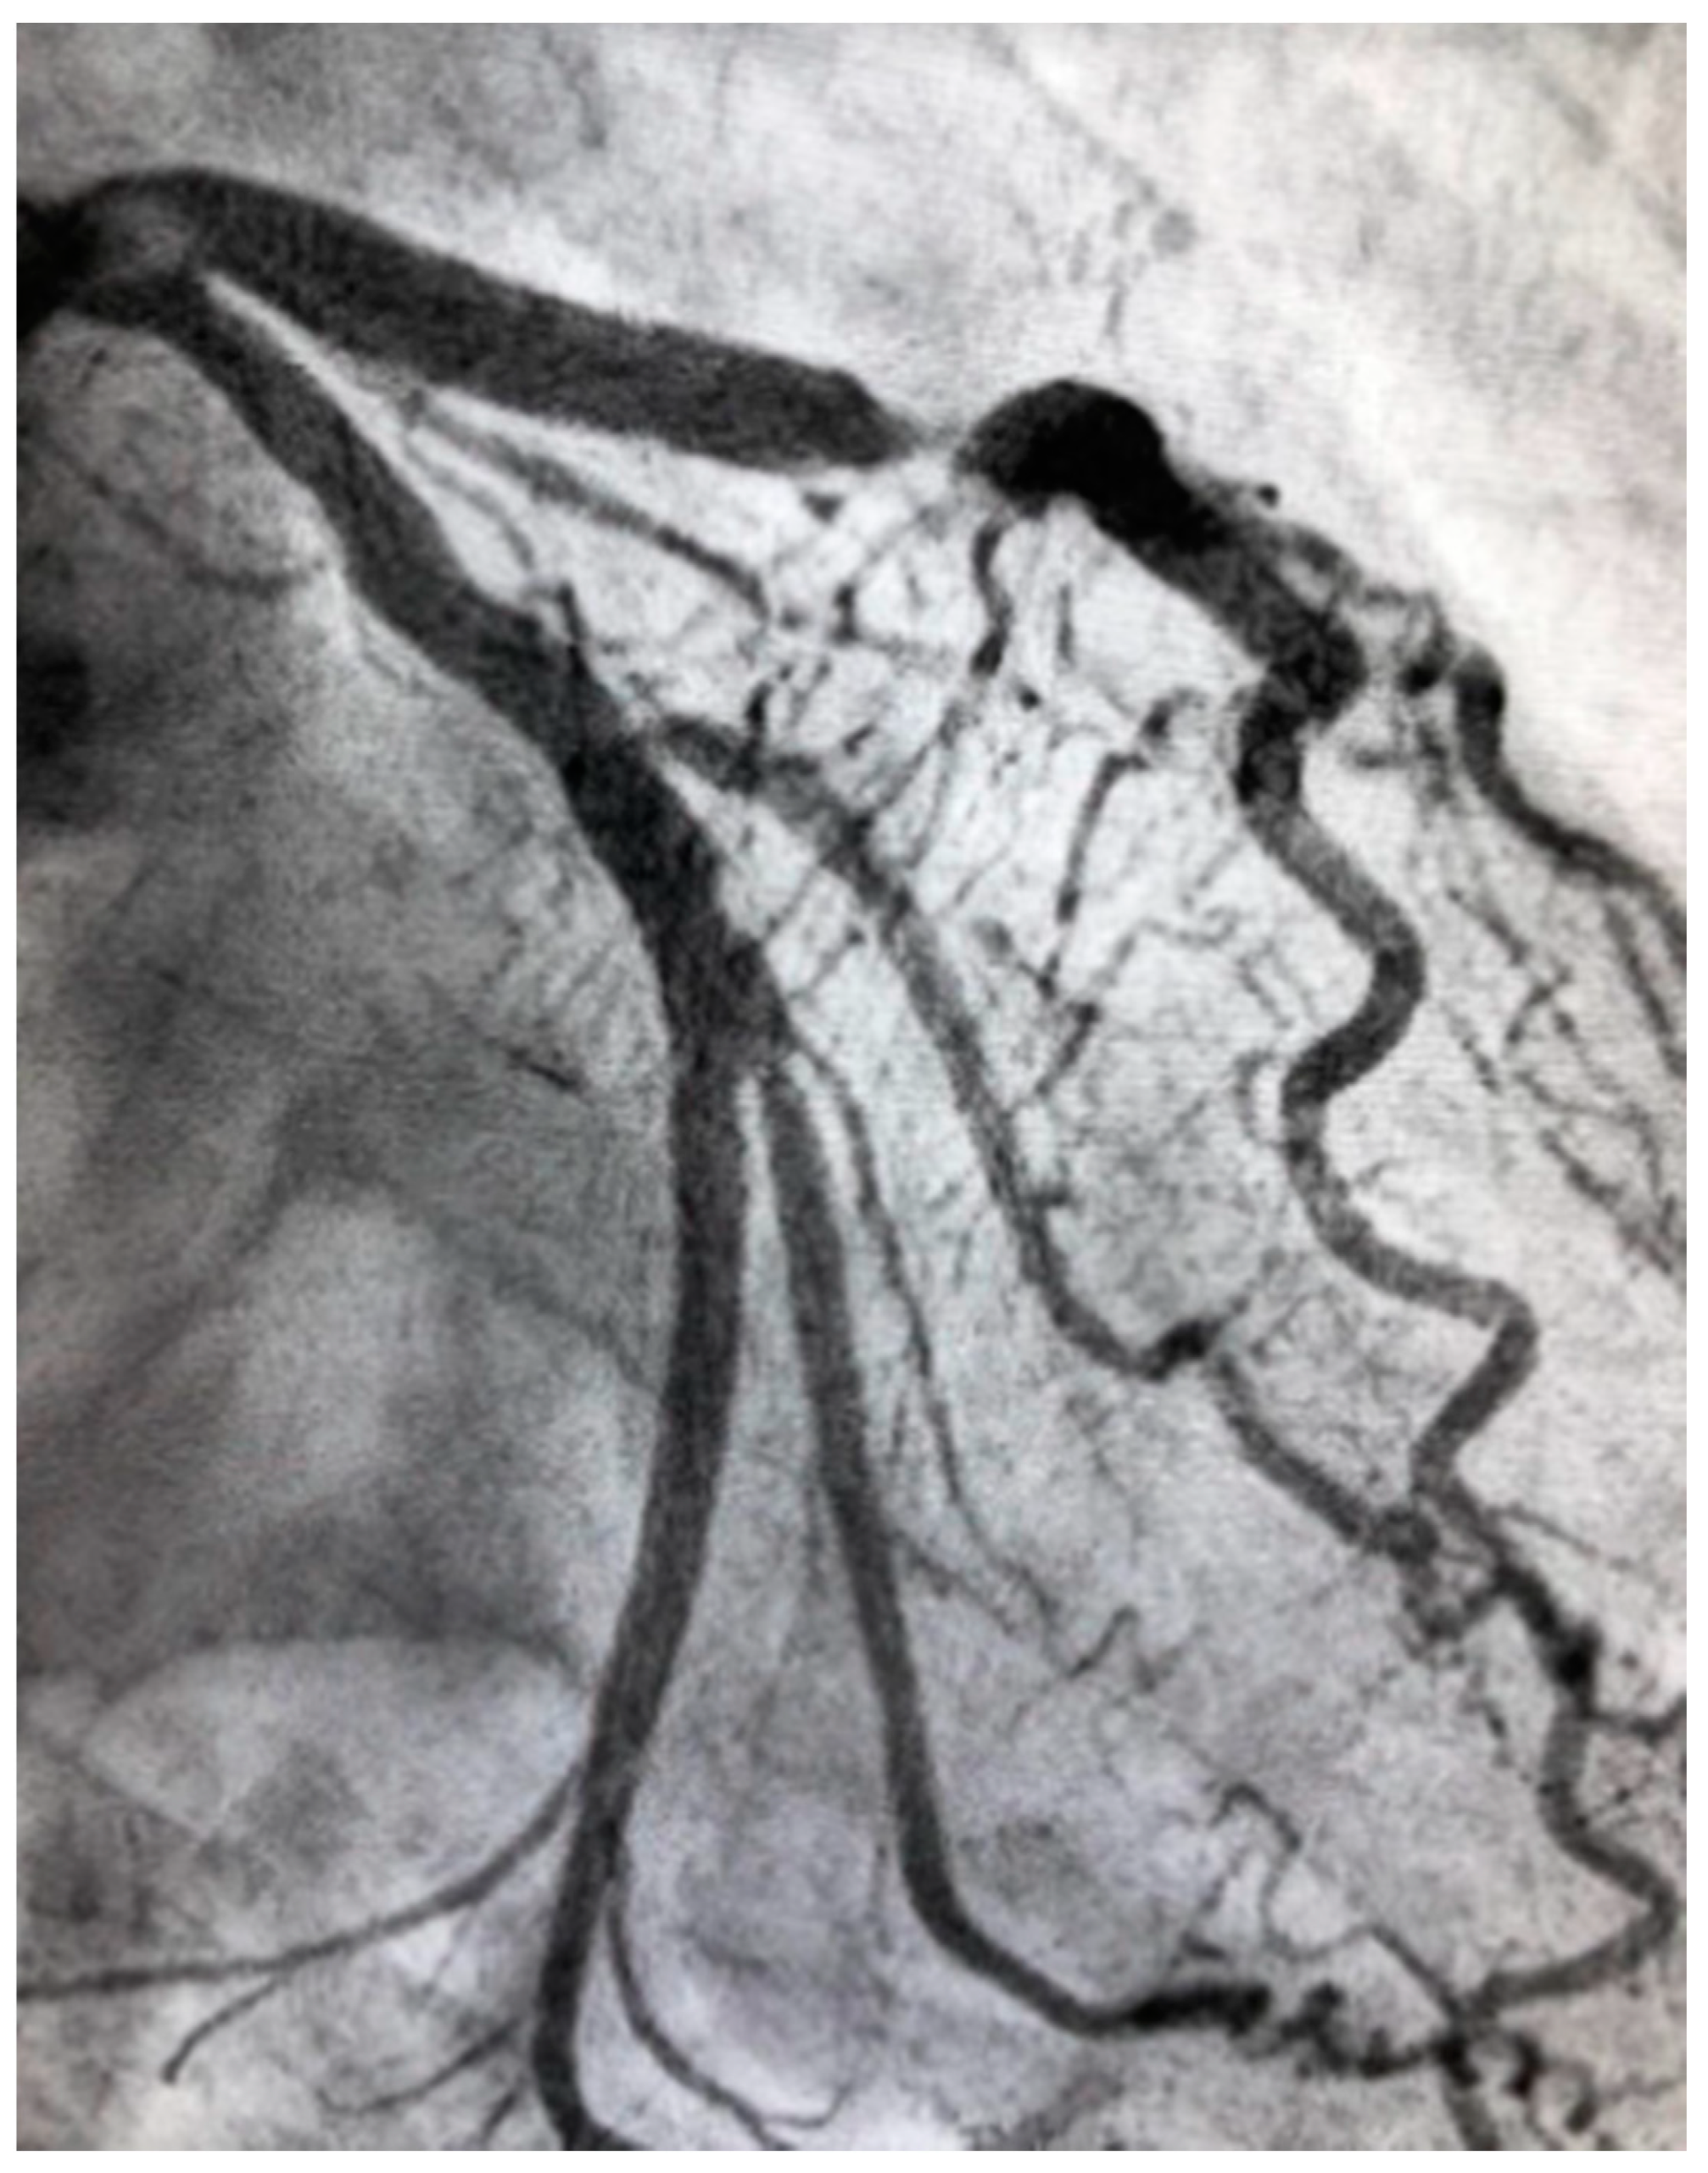

There is a growing body of evidence to show that vasculopathy in women with CAD is somewhat different and more severe compared to that in men. Atherosclerosis is often less extensive, and acute events are more frequently due to plaque erosion rather than plaque rupture (Figure 1 and Figure 2) [7,9]. Structurally, the coronary arteries themselves are of a smaller caliber size in women compared to men [10]. However, women and men have similar reference and lesion plaque burden, eccentricity, and calcium deposition in their atherosclerotic plaques [10].

Figure 2.

Severe atherosclerotic stenosis of the LAD in a female patient with ACS.